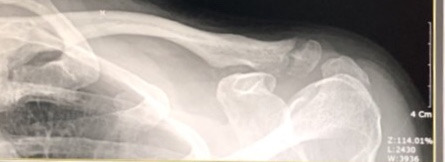

각각 7주차와 5주차의 엑스레이 영상 자료

촉진 중에 환부를 세게 눌러도 보셨는데 전혀 아프지 않았다. 엑스레이 영상에서는 아직 골갭이 보이지만 이건 차차 채워진단다. 완전히 하얗게 다 채워지는데 약 6개월 정도가 걸릴거라고 했다. 집에 와서 사진을 다시 확대해서 보니 희미하게나마 뼈모양대로 이어진 가골이 보인다.